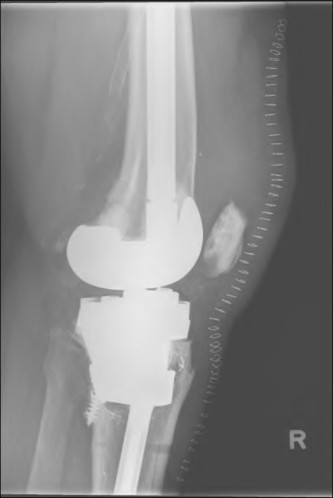

During a revision total knee arthroplasty, removal of the tibial component reveals a massive contained metaphyseal defect measuring 3 cm deep, but with an intact cortical rim. According to the Anderson Orthopaedic Research Institute (AORI) classification, what type of defect is this, and what is the preferred method of management?